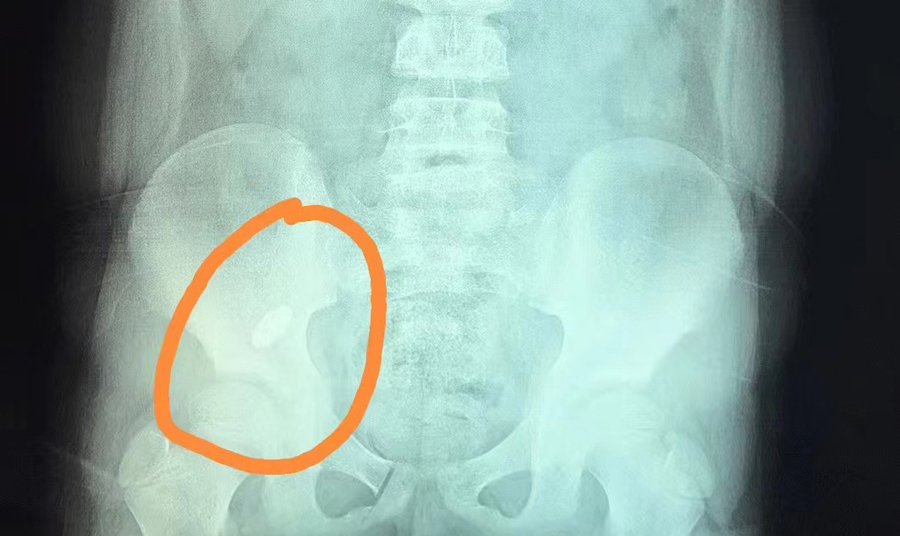

提醒那些认为孩子大了,就可以放松看管的家长:前段时间,长春8岁男孩俊俊(化名)因误吞一颗吸铁石,被家长紧急送到德州扑克游戏网 。内镜中心副主任边鹏首先对俊俊开具X线检查,确定异物位于右下腹。随后,她综合俊俊身体及异物情况,提出了先观察的建议,看异物是否能被排出,但是在俊俊复查时,发现异物位置并无变化。考虑到异物可能卡在回盲瓣且时间久,会导致局部黏膜损伤,边副主任建议手术取出异物。3月21日13时许,经过术前准备,内镜中心团队为俊俊进行全麻下异物取出手术。随着肠镜的深入,操作医生看到异物一半卡在了阑尾开口处,便利用异物网兜将异物取出,整个过程仅20分钟。阑尾开口处除了有充血水肿外,无其他异常。经过2天的住院治疗,俊俊痊愈出院。

俊俊算是比较幸运的,因为他吞下的是长约40mm、宽约10mm的椭圆形吸铁石,形状比较圆润,取出也算及时,对黏膜损伤不大。边副主任介绍,内镜中心接诊过各种各样的异物病例,总体看没有尖、刺、刃、毒、腐蚀性的异物,多为形状规则圆润且不太大的消化道异物,相对安全一些。如果异物能自然排出最好,反之则需及时通过镜下取出。